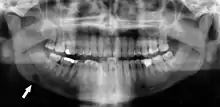

Panoramic radiograph showing horizontally impacted lower wisdom teeth.

Minimally-displaced fracture in right mandibular. Arrow marks fracture, root canal on central incisor, teeth to the left of fracture do not touch